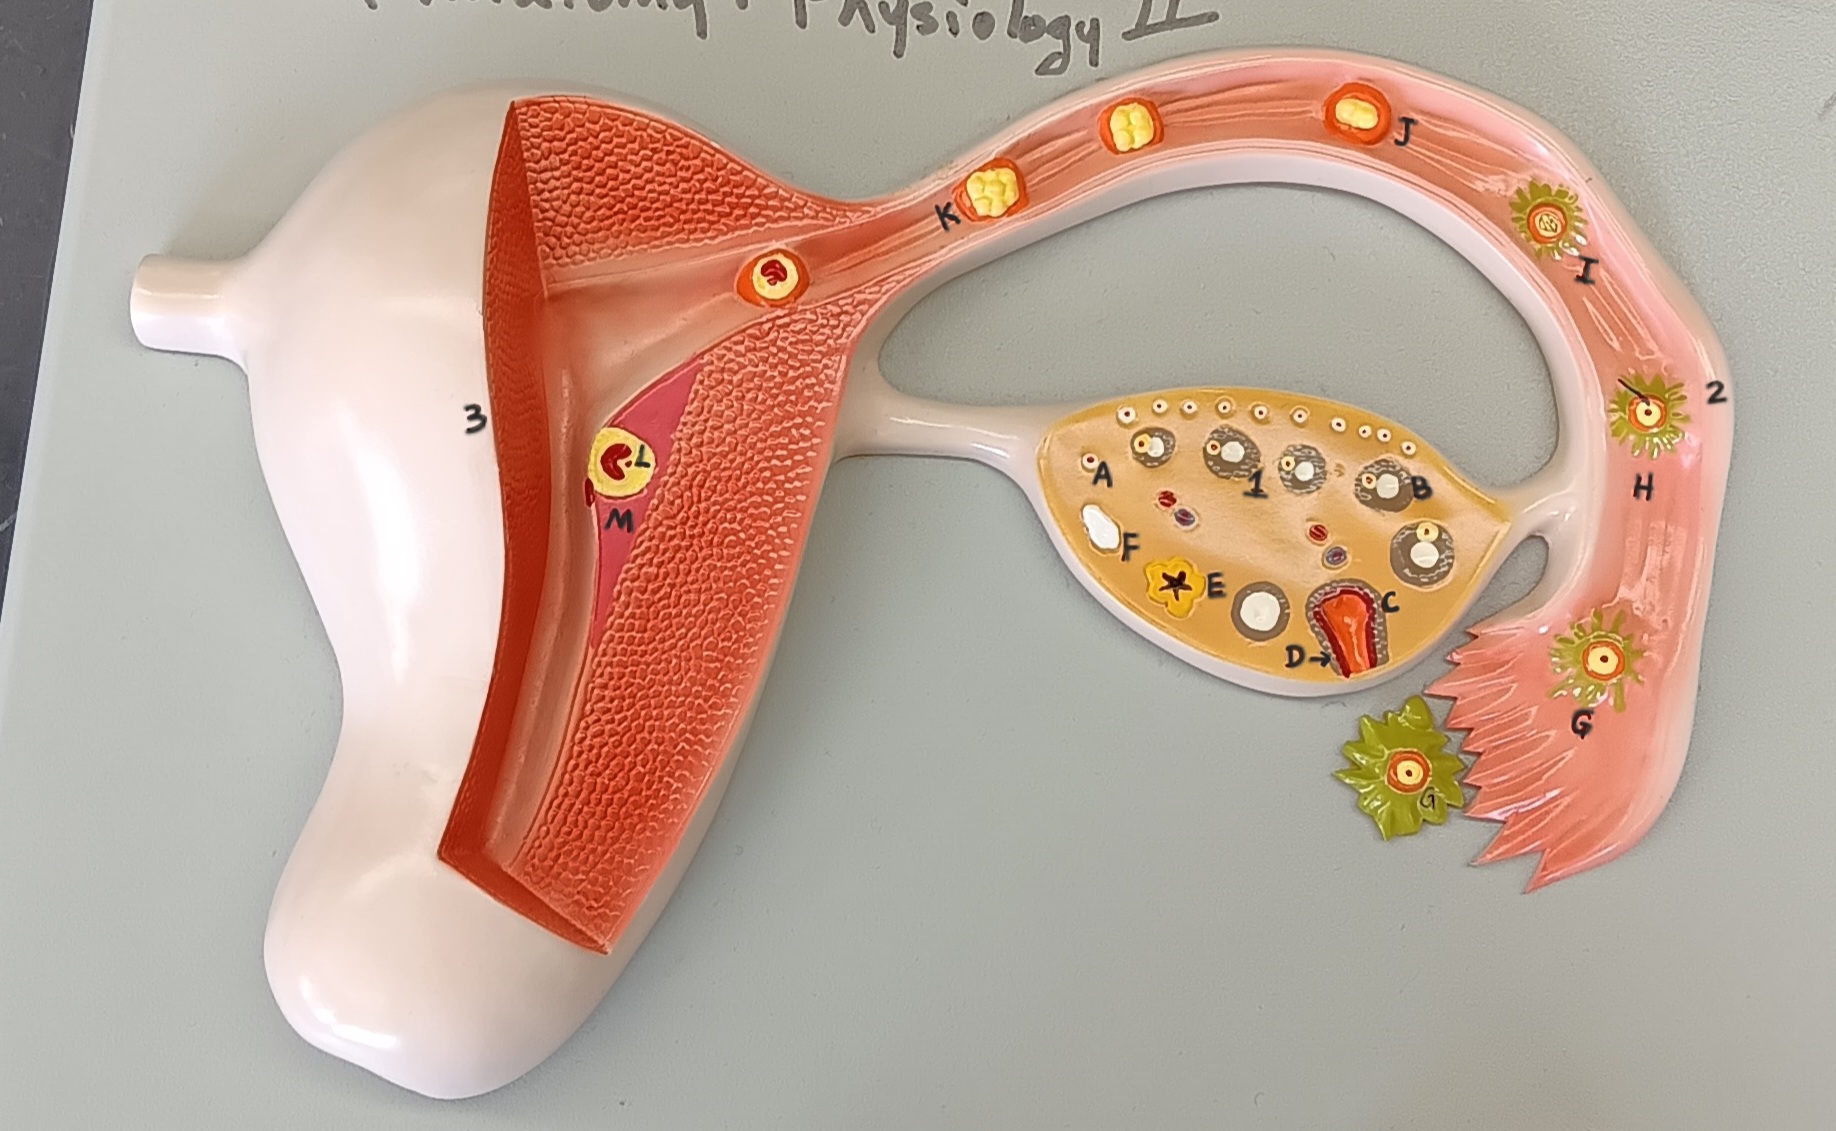

ovary

1

primordial follicle

a

secondary follicle

b

ruptured follicle

c

granulosa cells

d

corpus luteum

e

secondary oocyte

g

ovum

h

zygote

i

blastocyst

l

endometrium

m

corpus albicans

f

uterus

3

fallopian tube

2